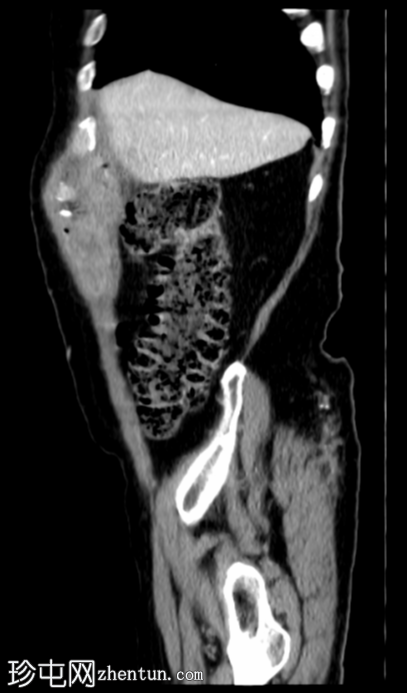

矢状位增强扫描

门静脉期

胆囊底部可见一枚较大的(3厘米)高密度结石,胆囊壁增厚并强化,主要位于胆囊底部。胆囊壁可见一小穿孔,感染扩散至胆囊外,并在肝下区可见气体腔。感染进一步扩散至腹壁肌肉,腹壁肌肉内可见脓肿,边缘强化明显,囊性坏死中心,腔内可见气体腔。十二指肠第一段与炎症胆囊粘连。

检查结果提示急性胆囊炎合并腹壁脓肿。